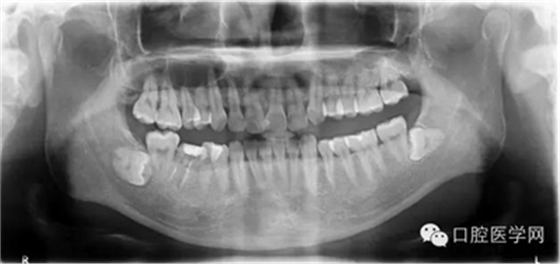

輔查:曲面斷層觀察齒c槽隔情況,為種植支抗植入熟悉解剖。